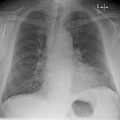

Kerley B lines in acute cardiac decompensation. The short, horizontal lines can be found everywhere in the right lung.

Chronic stable heart failure may easily decompensate. This most commonly results from a concurrent illness (such as myocardial infarction (a heart attack) or pneumonia), abnormal heart rhythms, uncontrolled hypertension, or a person's failure to maintain a fluid restriction, diet, or medication.[31] Other factors that may worsen CHF include: anemia, hyperthyroidism, excessive fluid or salt intake, and medication such as NSAIDs and thiazolidinediones.[32] NSAIDs increase the risk twofold.[33]

Chest X-ray

Chest radiograph of a lung with distinct Kerley B lines, as well as an enlarged heart (as shown by an increased cardiothoracic ratio, cephalization of pulmonary veins, and minor pleural effusion as seen for example in the right horizontal fissure. Yet, no obvious lung edema is seen. Overall, this indicates intermediate severity (stage II) heart failure.

Chest X-rays are frequently used to aid in the diagnosis of CHF. In a person who is compensated, this may show cardiomegaly (visible enlargement of the heart), quantified as the cardiothoracic ratio (proportion of the heart size to the chest). In left ventricular failure, evidence may exist of vascular redistribution (upper lobe blood diversion or cephalization), Kerley lines, cuffing of the areas around the bronchi, and interstitial edema. Ultrasound of the lung may also be able to detect Kerley lines.[43]